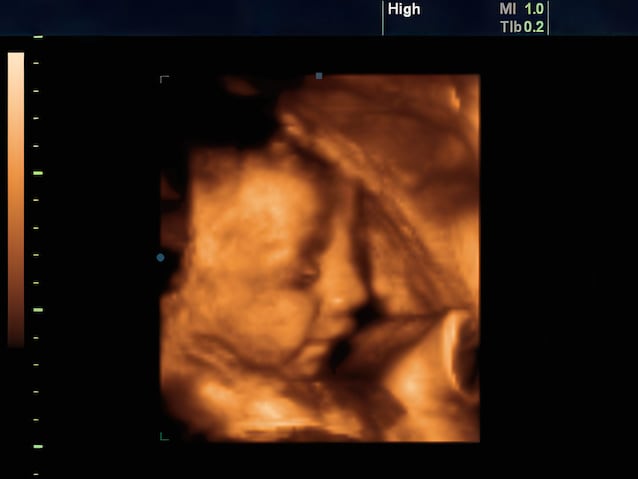

In a study published in 2022 in the magazine Psychological Science from a team ofDurham Universityusing 4D ultrasound, the researchers managed to observe the facial expressions of the fetuses between the 32nd and 36th week After the mothers had ingested capsules flavored to the carrot or al cabbage hedgehog. After about 30 minutes from the ingestion of the carrot capsule – a sweet taste, usually associated with positive reactions already in infants – the fetuses showed expressions similar to a smile. On the contrary, after the capsule with the hedgehog – a more bitter taste and usually little appreciated also by the children – they exhibited Rooms corrugatedas if to report an unwelcome taste.